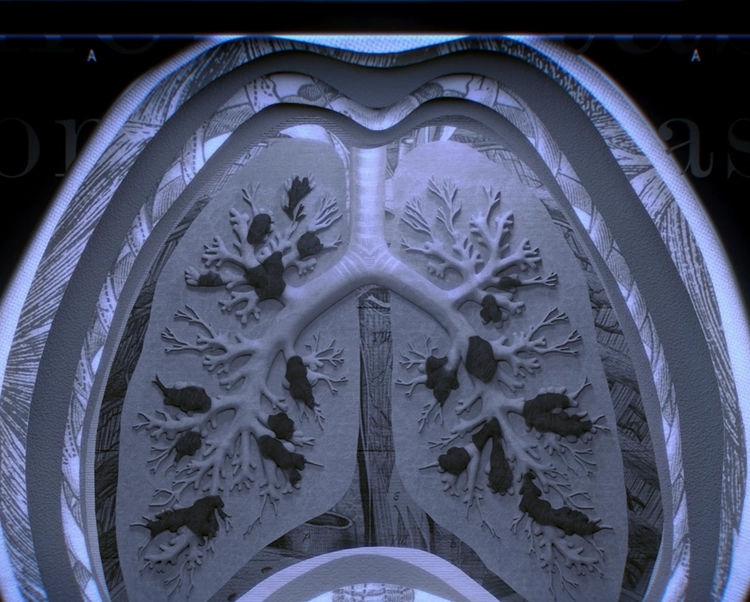

A CT scan is the standard way to determine if you have bronchiectasis.

A CT scan can rule out or confirm bronchiectasis.

A CT scan is a type of chest scan that provides clear, detailed images of the lungs. It’s used to diagnose BE because it can reveal widening of the bronchi—a sign of the disease that tests like an X-ray might miss.

A CT scan of a lung with bronchiectasis